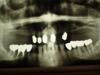

Langjährige Kieler Patientin erhält neue Unterkieferfrontzahnbrücke

Die Oberkieferteleskoparbeit hat die Patientin inzwischen fast 25 Jahre im Mund und die Unterkieferfronzahnbrücke könnte das ebenfalls erreichen.